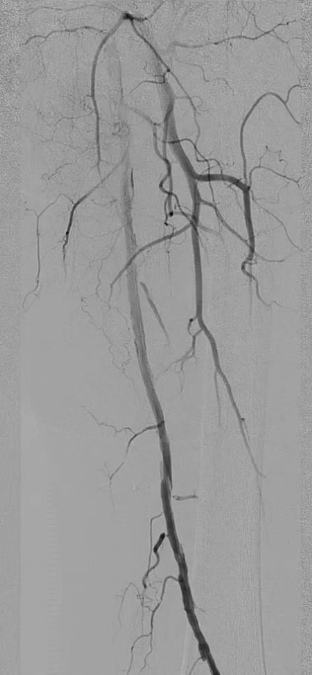

左侧股浅动脉中上段明确长段狭窄并闭塞,病变长度约15cm,股浅动脉远段至腘动脉管腔通畅。

膝下动脉三支主干均闭塞,胫后动脉远端经侧支循环显影;腓动脉远端为“休眠血管”,通过与胫后动脉的交通支实现逆向显影。